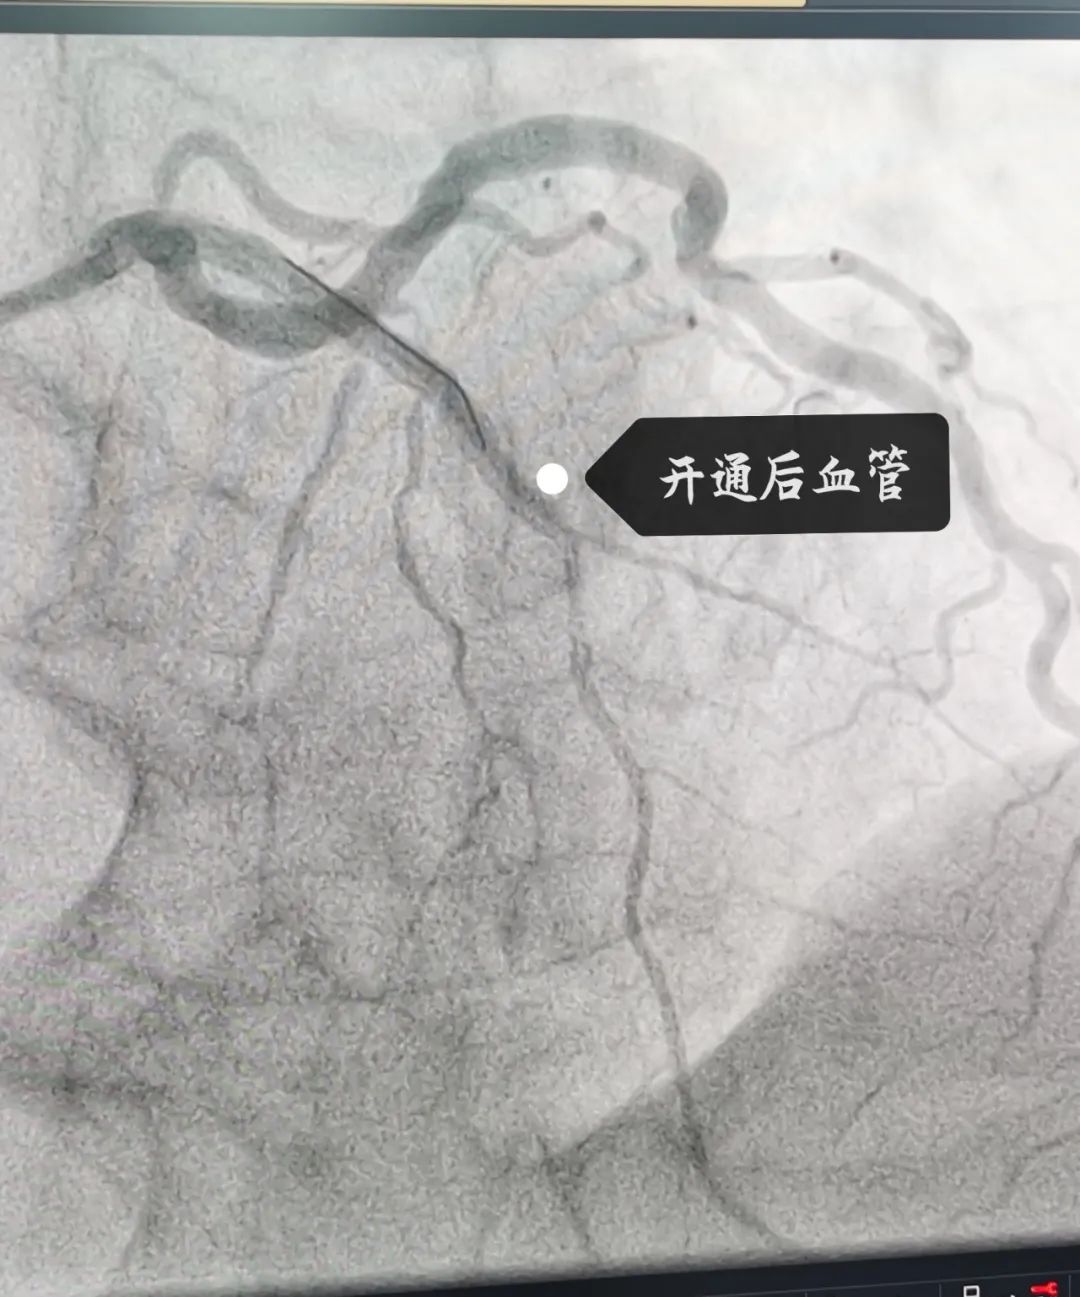

这位患者是位90后,因突发胸闷持续20余小时才来医院治疗,考虑到小伙子胸痛反复,无法缓解,病情危急,九龙湖院区心内科团队立即查找原因,原来小伙子最重要的一支心脏血管:“前降支”急性闭塞且血栓负荷重。于是,球囊扩张、血管内溶栓、支架植入......紧张又有序地手术操作结束后,小伙子闭塞的血管终于打通,胸痛症状也得到了明显缓解。

可是,张叔叔明明年纪不大,为什么一个呼吸道感染就会导致心衰这么危险的疾病呢?原来,张叔叔的心脏血管“前降支”出现了慢性闭塞。于是,心内科手术团队在血管内超声指导下精准植入2枚支架,使张叔叔的前降支血流恢复畅通。手术后,张叔叔的胸闷症状明显缓解,运动耐力也明显恢复,射血分数也由术前的42%显著回升到50%。